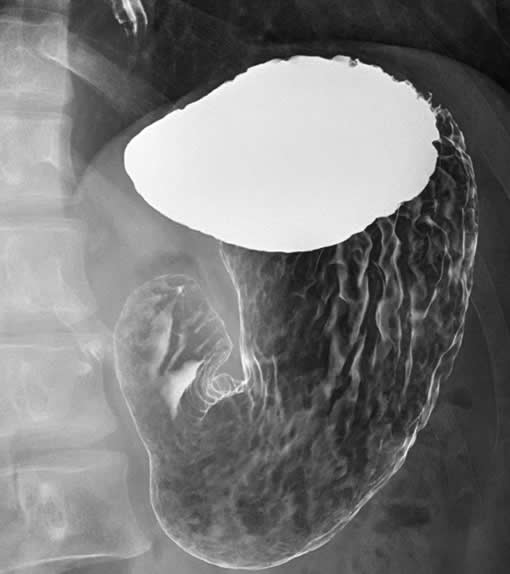

X線透視撮影

X線TV装置とは、体を透過したX線をモニターで、リアルタイムに動画として見ることができます。

当院では、食道、胃、大腸などの消化管造影検査などを行っております。

胃透視